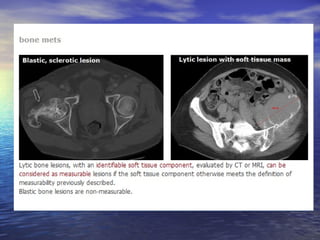

Lesões não mensuráveis